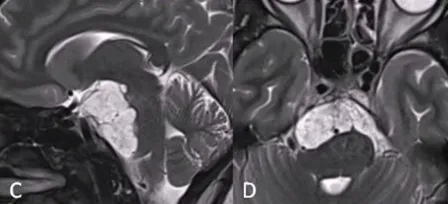

26岁女性,阵发性复视,进行性左外展神经麻痹,MRI显示斜坡巨大脊索瘤,病变浸润性生长,肿瘤延伸浸润至乙状窦(SS)、左侧海绵窦(CS)、下斜坡到脑干脚间池硬膜部分(图A、B)。

该名女士找到INC福教授进行手术,第一期手术,福教授采用联合内镜鼻内入路(EEA)切除硬膜外部分重量,对于硬膜内部分肿瘤采用经颅入路,以降低脑脊液漏和神经血管损伤的风险。

首先,进行内镜鼻内活检,显示典型的脊索瘤。然后,她接受了内镜经鼻入路手术,从硬膜外部分切除到斜坡和海绵窦部分的肿瘤(图C、D)。

2个月后,进行第二次手术,使用右侧mini经岩骨入路切除硬膜内肿瘤。术后MRI显示肿瘤完全切除GTR(图E、F)。术后接受了质子束治疗(PBT)。5个月随访时,她的神经系统检查正常,头面部外观美容效果也非常好。